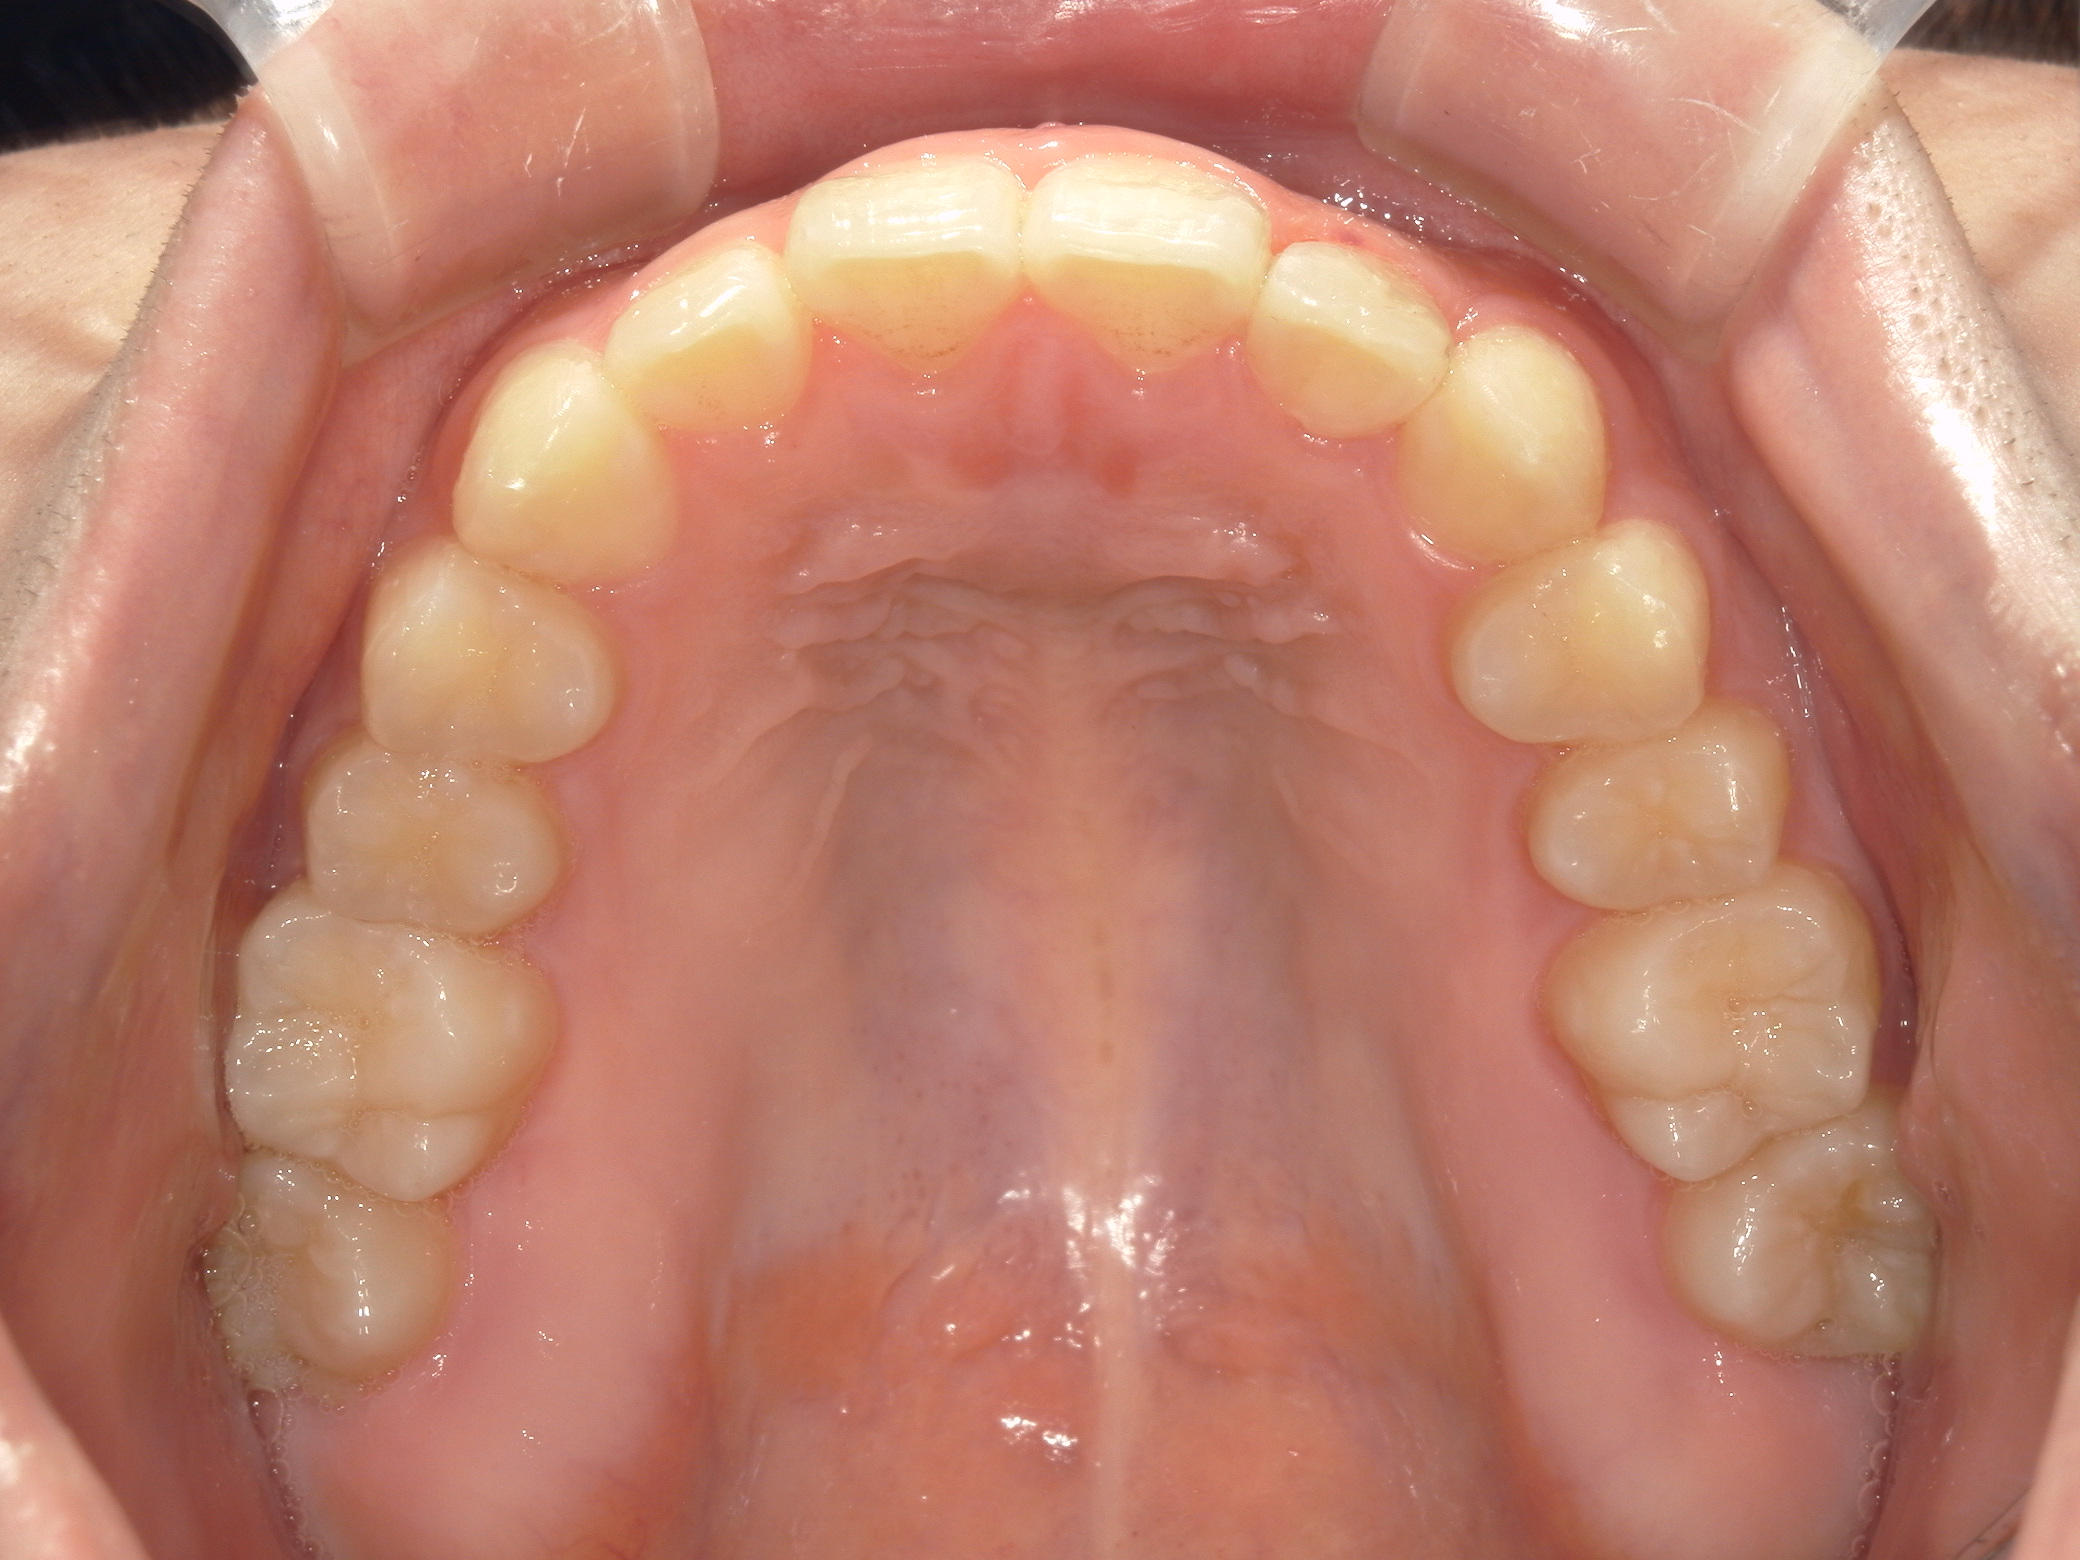

インビザライン矯正 症例(19)

主訴: 左上犬歯が出ているのが気になる